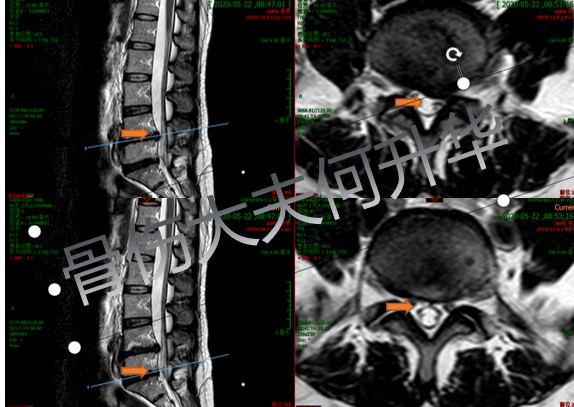

入院后MRI横断面片显示腰椎左侧4/5

椎间盘突出症,腰椎 5 骶骨 1 椎间高度下降